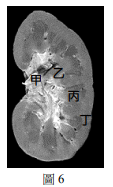

112分科生物考科-29